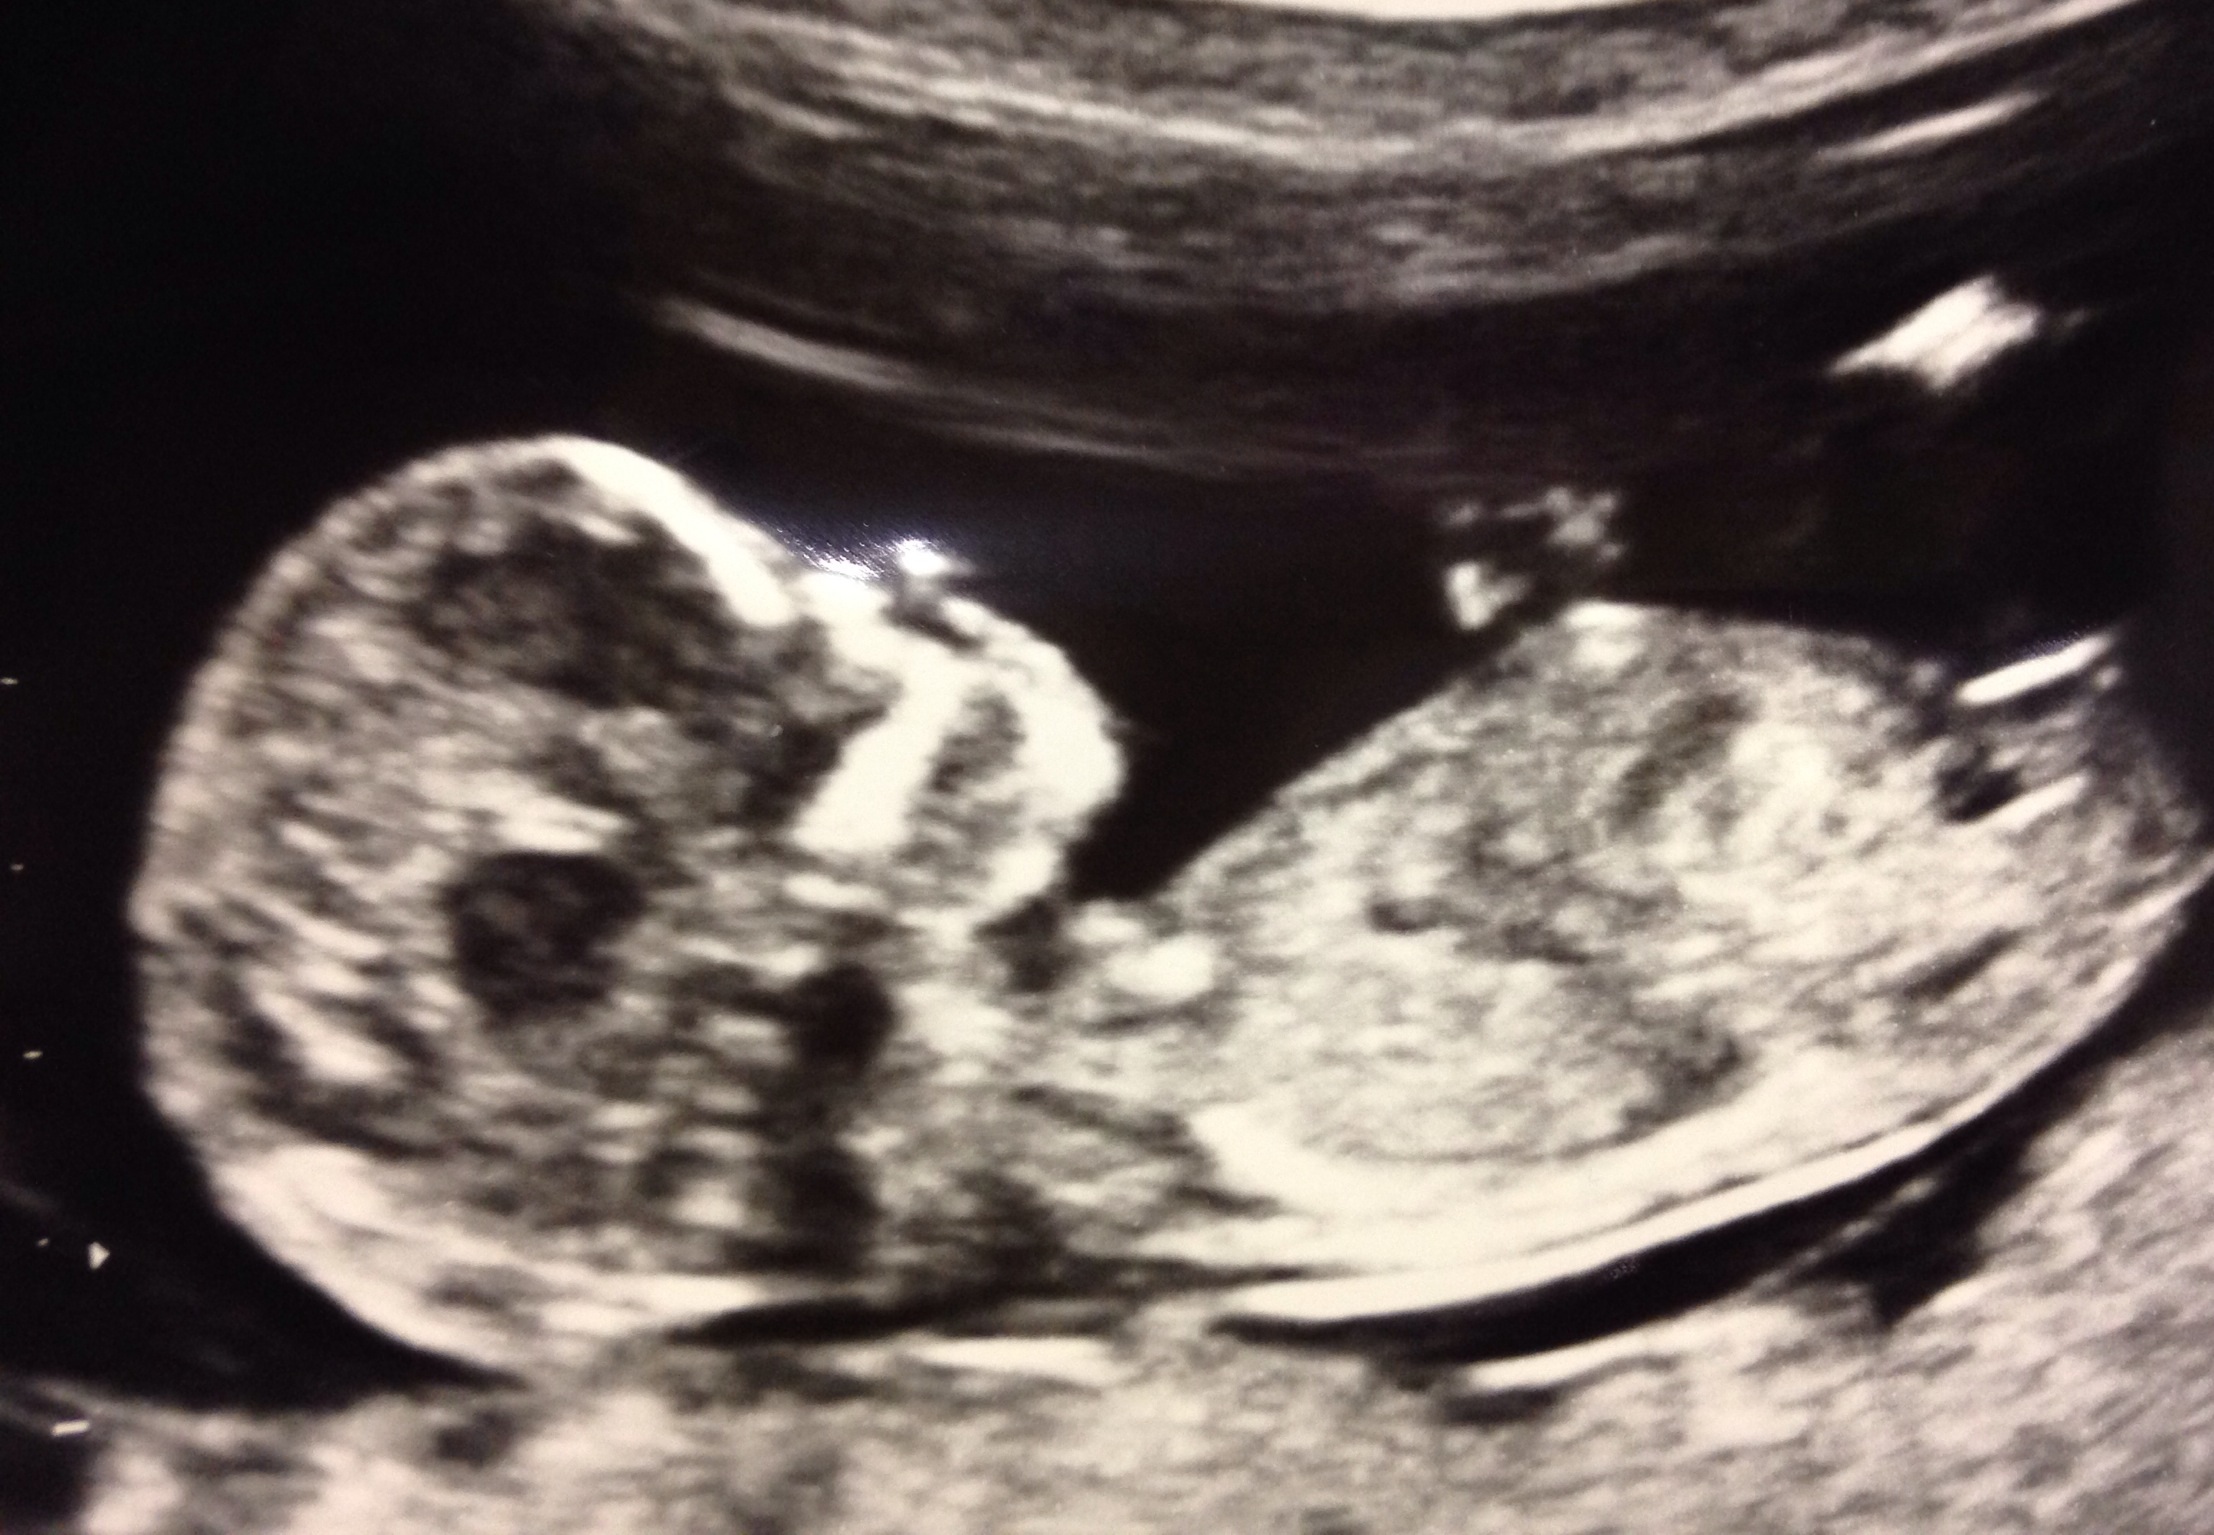

Here is our scan pics from 12 weeks 5 days i cannot wait to find out at 16 weeks the sex of the baby please can I have your guesses based on the nub and skull theory as I cannot work it out xxAttachment 16923Attachment 16924

I don't like guessing by skull, but the nub looks very girly!!

Nub looks very girly!

Girl by nub

Looks pink by nub :)